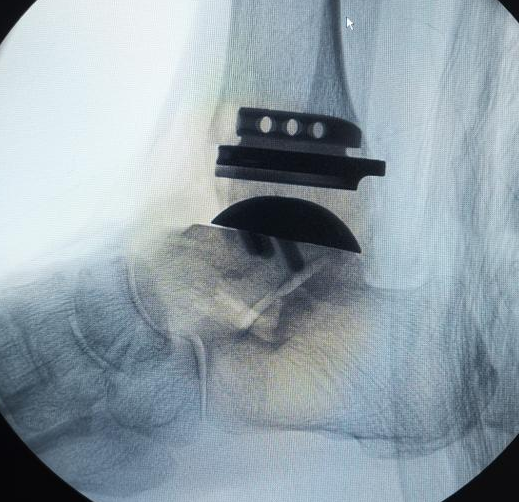

兰大二院骨科开展甘肃省内首例3D打印导航下国产全踝关节置换手术

近日,兰大二院成功为一名踝关节骨性关节炎患者实施3D打印导航下的国产全踝关节置换手术,填补了甘肃省内足踝外科领域的技术空白,为甘肃省及周边地区的广大患者带来了福音。

患者男性、54岁,常年因踝关节慢性疼痛而困扰,曾就诊多家医院无果,病情逐渐加重,已经严重影响患者的运动功能和生活质量。遂来兰大二院骨科就诊。骨科四病区副主任医师王凯接诊后立即完善相关检查明确诊断。结合病人的实际情况经科室讨论后,选择3D打印导航下的国产全踝关节手术治疗方案,在病区主任刘京升的指导下,为患者实施了手术治疗,术后恢复良好,现已康复出院。